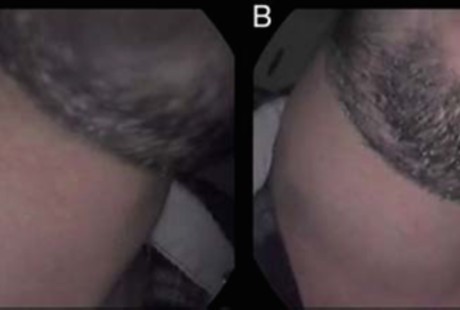

Sang pria kemudian diminta untuk bermain trompet sambil dipindai ulang. Hasilnya dokter menemukan ada area tak normal di leher pasien yang membesar ketika meniup trompet dan dugaan sementara karena pharyngocele. Orang dengan kondisi ini otot di area pharynxnya lemah akibat sering berada di bawah tekanan sehingga bisa menggelembung ketika ia meniup. Keluhan pharyngocele di antaranya batuk-batuk, sulit menelan, muntah, dan nyeri.

Namun ada penyakit lain yang serupa yaitu laryngocele, bedanya otot lemah dan penggelembungan terjadi di area kotak suara. Edmiston mengatakan kotak suara orang dengan kondisi ini juga menggelembung oleh udara karena sering berada di bawah tekanan dalam waktu lama. keluhan laryngocele di antaranya suara serak dan sulit bernapas.